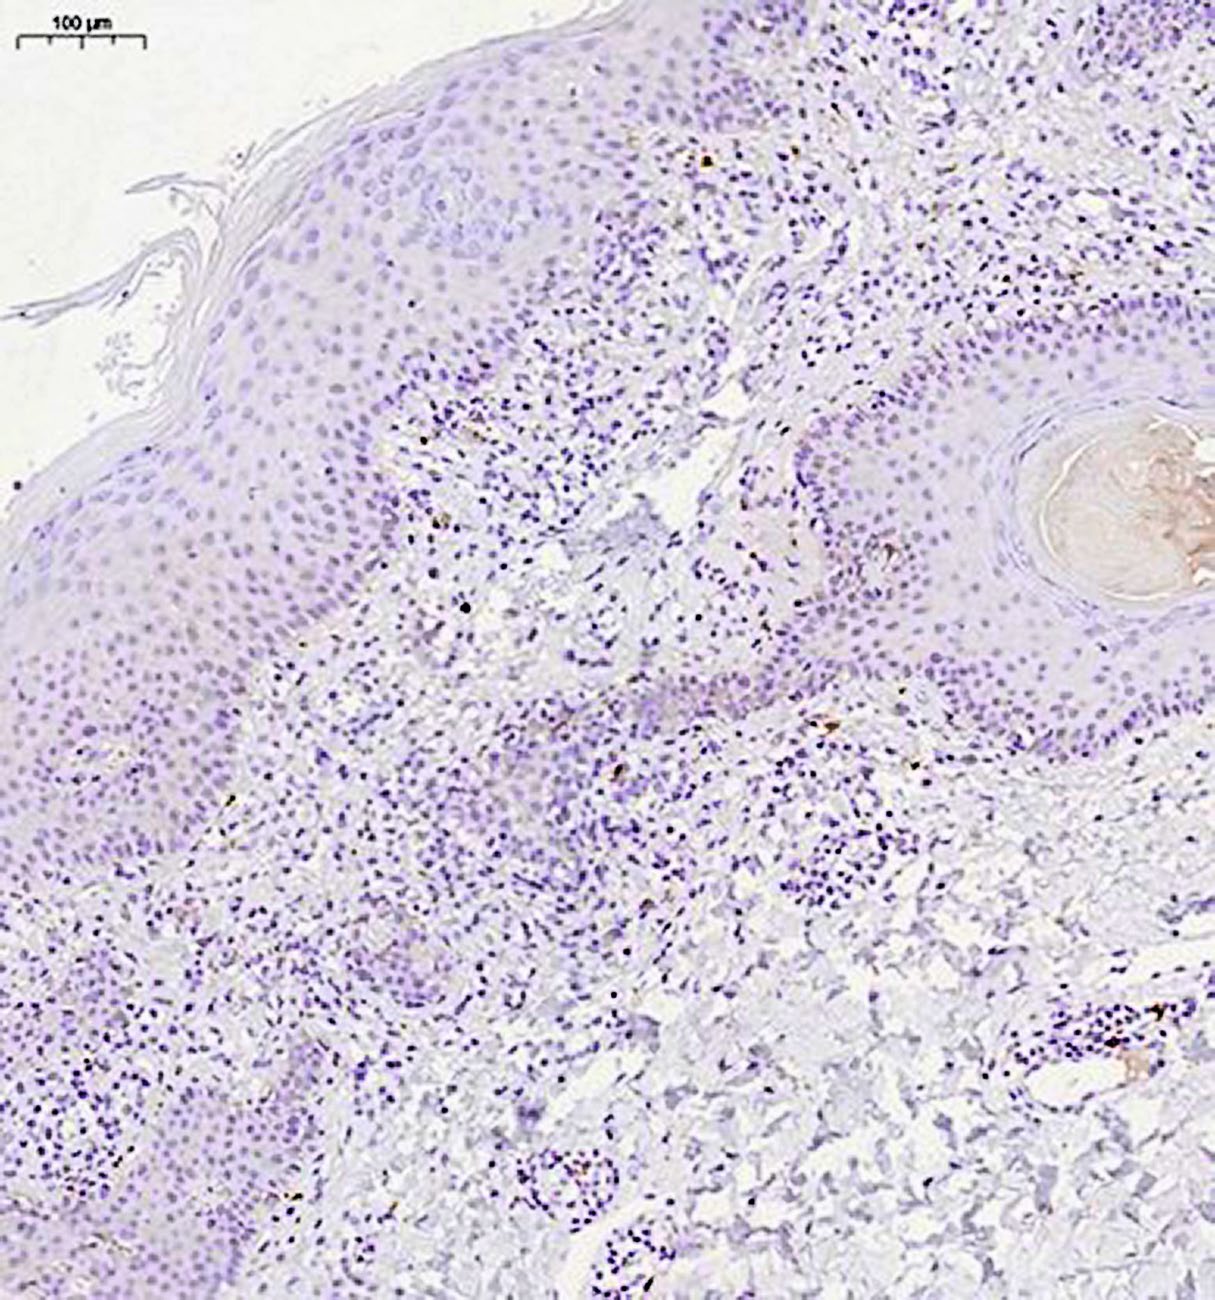

При иммуногистохимическом исследовании антиген пролиферативной активности Ki-67 экспрессирован в ядрах примерно 30% клеток воспалительного инфильтрата, в эпидермисе экспрессия Ki-67 не ограничена клетками базального слоя, а видна в более высоких слоях (рис. 5). Лимфоидные клетки инфильтрата экспрессируют CD3, CD5, соотношения CD4 и CD8 позитивных клеток соответствуют примерно 1:1 (рис. 6, 7). Единичные клетки экспрессируют CD20 (рис. 8). Заключение: клиническая картина заболевания, обнаруженные морфологические изменения в коже и результаты иммуногистохимического исследования в наибольшей степени соответствуют атипичной форме красного волосяного лишая Девержи.

Рис. 8. Иммуногистохимическое исследование с антителами к CD20, ×100